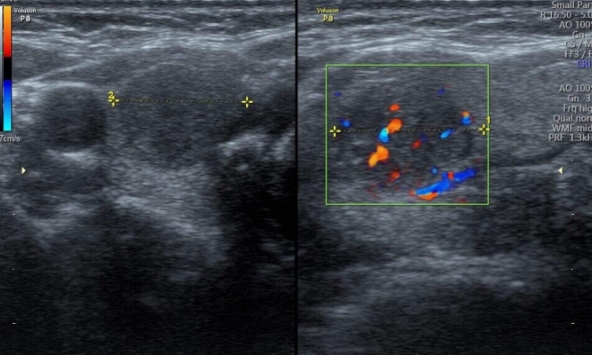

| Người phụ nữ luôn tưởng mình khỏe mạnh nhung vô tình phát hiện ung thư tuyến giáp khi khám sức khỏe tại công ty (Ảnh minh họa) |

Vương Hân kể lại, cô luôn cho rằng đánh giá sức khỏe tại công ty chỉ qua loa, mang tính chất giấy tờ. Nhưng vị bác sĩ đó luôn để ý đến cổ của Vương Hân kể từ khi cô bước vào phòng. Cuối cùng, ông yêu cầu cô tới bệnh viện lớn để khám sâu hơn vì nghi ngờ có nốt tuyến giáp.

Cô vẫn rất chủ quan vì mình không có triệu chứng gì bất thường nhưng chồng cô thì bắt đầu lo lắng. Dưới sự thuyết phục của anh, cuối cùng cô cũng chịu đến Bệnh viện tuyến giáp Côn Minh Zhongyan (Côn Minh, Trung Quốc). Kết quả sinh thiết chỉ ra cô bị ung thư tuyến giáp thể nhú giai đoạn 2. Mặc dù rất sốc nhưng cô nhanh chóng quyết định phẫu thuật để trở lại với công việc và cuộc sống hàng ngày.